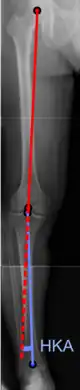

Hip-knee-ankle angle.

There are two disorders relating to an abnormal angle in the coronal plane at the level of the knee:

• Genu valgum is a valgus deformity in which the tibia is turned outward in relation to the femur, resulting in a knock-kneed appearance.

• Genu varum is a varus deformity in which the tibia is turned inward in relation to the femur, resulting in a bowlegged deformity.

The degree of varus or valgus deformity can be quantified by the hip-knee-ankle angle,[36] which is an angle between the femoral mechanical axis and the center of the ankle joint.[37] It is normally between 1.0° and 1.5° of varus in adults.[38] Normal ranges are different in children.[39]